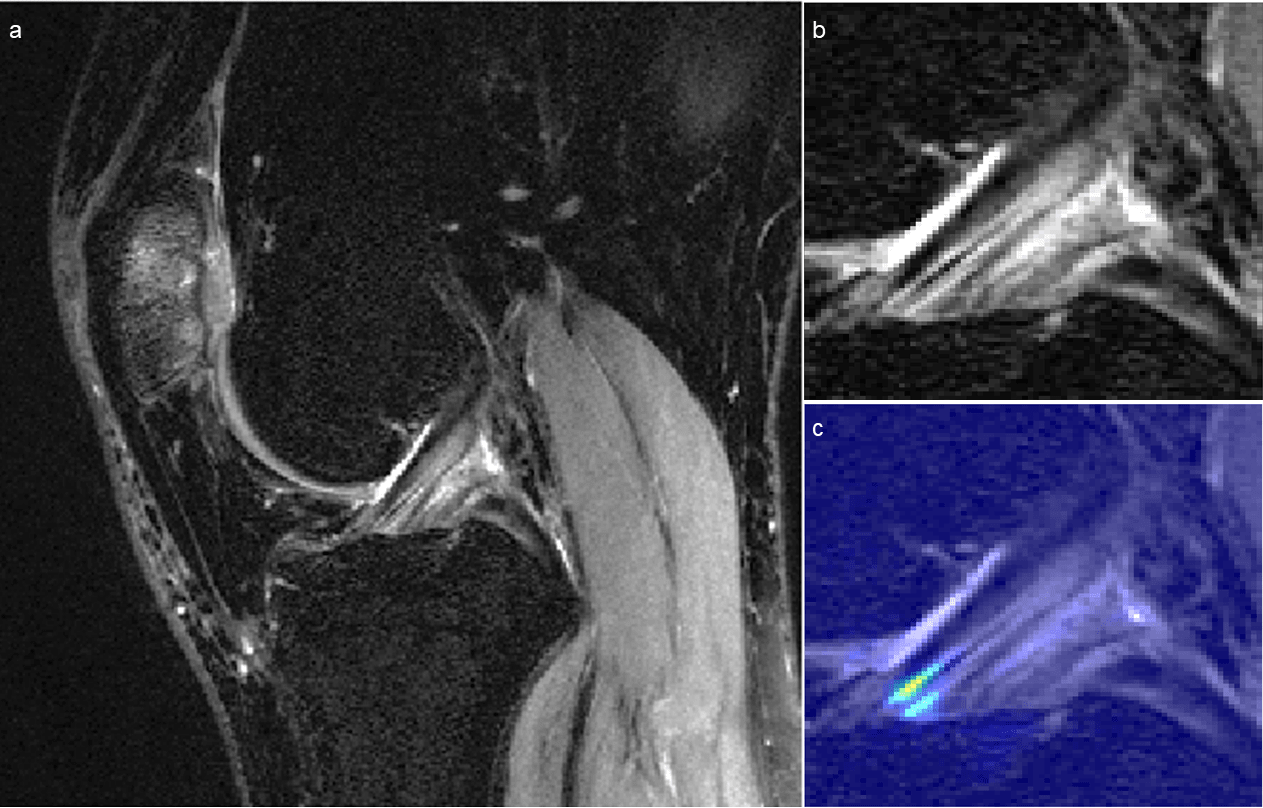

Figure 5 displays a knee with intact ACL that was input into the pipeline, followed by localization of the ACL and the corresponding saliency map generated by the model’s classification weighting. Saliency maps were generated from the 3D CNN’s rectified linear unit output in its last dense layer. This ACL was correctly classified and possesses a high intensity on the inferior portion of the ligament’s saliency. An incorrectly classified intact ACL, predicted to be partially torn, is seen in Figure 6. The model placed a high intensity on a sagittal view with overlapping ACL and femur signal. The resulting saliency possessed large weight on a portion of the joint posterior to the ligament and also has speckles of noise further posterior. The 3D CNN took less than one second to classify a single ACL that went through all three hierarchical classifiers.

Refer to caption

Figure 5: Sagittal views of (a) correctly classified knee with intact anterior cruciate ligament (ACL) and (b) its ACL localization with (c) overlaid saliency map. The saliency demonstrates the anterior-inferior portion of the ACL as high importance for model classification.